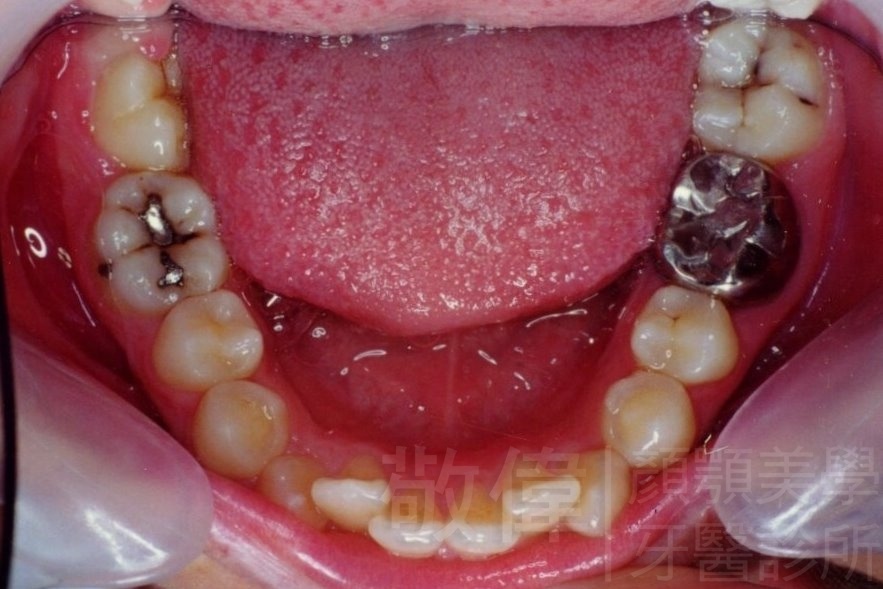

矯正前-上   矯正前-下

矯正後-上   矯正後-下

戽斗(學名第三級咬合 class III)矯正之後,戽斗的樣子就比較沒有了。最主要的改變是在牙齒的咬合。從側面比較,治療前、治療後的臉型 可更明顯看出來 戽斗的感覺 減少了很多。